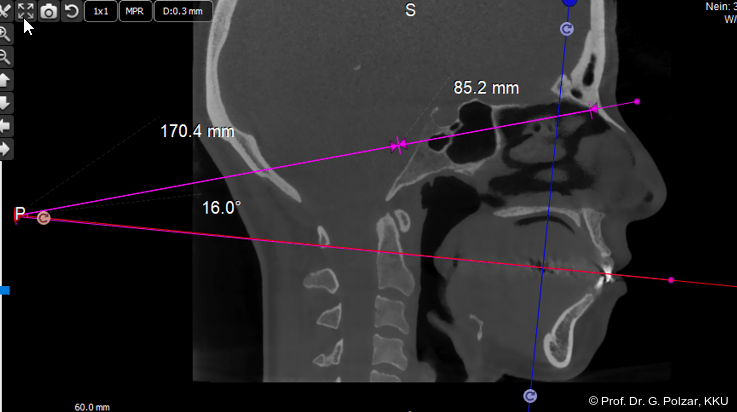

Mit der von Hornung/Polzar entwickelten CranioPlan-Analyse ist es möglich, alle Positionen im dreidimensionalen Raum exakt zu vermessen und in Relation zum afferent-physischen Zentrum jedes einzelnen Patienten zu bestimmen.

Der zentrale Punkt, von dem die Messungen ausgehen, ist die Mitte zwischen rechtem und linkem Gleichgewichtsorgan. Bei unserer ersten Definition des Mittelpunktes sind wir (2016) von der Mitte des Abstandes der beiden Inci vestibulari ausgegangen, da dieser im DVT mittlerer Auflösung leicht zu bestimmen ist (Abb. 21).

Exakter ist jedoch die Bestimmung des zentralen Wahrnehmungs­ortes des Gleichgewichtsorgans, der Macula sacculi. Diese befindet sich im Sacculus vestibularis der jeweiligen Seite. Die Mitte der Linie zwischen dem Sacculus vestibularis dexter und sinister ist dann der ursprüngliche Nullpunkt der CranioPlan-Analyse. Dieser Punkt liegt etwas posterior zur Mitte der Hammerknöchelchen und gibt den exakten OriginPoint (O-Punkt) als Ausgangspunkt der afferenten Sym­metrieachse an (Abb. 22–24).

Die zu bildende Fläche (CranioPlan) wird nun auf den Mittelpunkt der Bipupillarlinie zentriert. Verlängert man diese Fläche um das Drei­fache nach dorsal und verbindet das hintere Ende mit der Okklusionsebene, so erhält man einen Winkel, der dem Winkel der Frankfurter Horizontale (Orbitalpunkt/Tragionslinie) mit der Okklusionsebene entspricht. Da diese Grundlinie der Frankfurter Horizontalen nicht so genau bestimmt werden kann, sind die Bezugswerte der CranioPlan-Analyse wesentlich genauer und auch leichter reproduzierbar (Abb. 25).